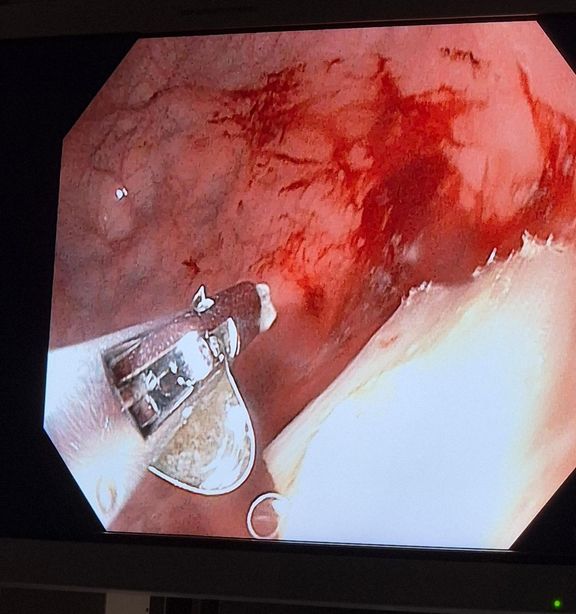

"U tří malých pacientů jsme museli provést urgentní endoskopický zákrok, ve zbylých případech byly děti sledovány při hospitalizaci až do samovolného odchodu cizího tělesa. Kovový plíšek má ostré hrany a může poškodit trávicí trakt, v krajním případě by mohlo dojít i k perforaci," upozorňuje lékařka Kristýna Zárubová z Oddělení dětské gastroenterologie Pediatrické kliniky 2. LF UK a FN Motol.

Zákroky probíhaly i ve spolupráci s Interní klinikou 2. LF UK a FN Motol. Díky rychlé lékařské intervenci se ve všech případech podařilo předejít nutnosti chirurgického výkonu. Produkty pro užívání zahřívaného tabáku fungují na principu zahřívání speciálních tabákových náplní. Na rozdíl od klasických cigaret při jejich používání nedochází ke spalování, ale k tvorbě aerosolu obsahujícího nikotin.